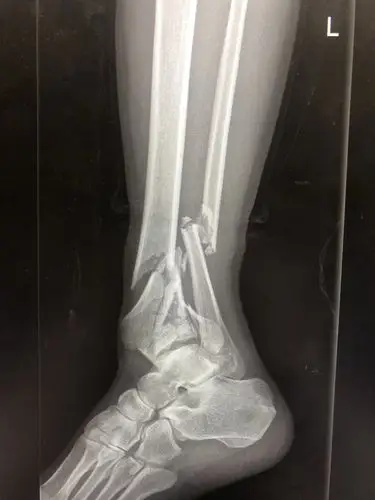

胫腓骨远端粉碎性骨折